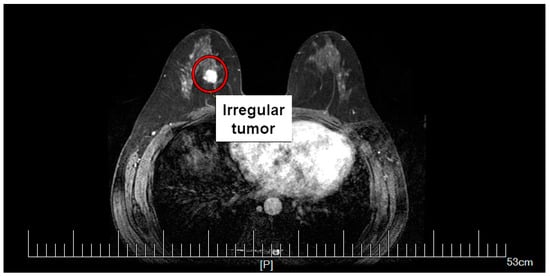

To present the problem in the most realistic way, the calculations were performed using an anatomically correct model of the female breast with an irregularly shaped tumor. The breast tumor was screened at Dalian University of Technology, China. The mammography scan can be seen in Figure 1, together with the tumor marked with a red circle. From the mammogram, the irregular tumor was extracted and placed in the anatomically correct model of the female breast, as shown in Figure 2. The model of female breast tissues was adapted for numerical calculations from a breast phantom repository provided by the University of Wisconsin—Madison []. It consisted of skin, fibroconnective/glandular-1,-2,-3, transitional, fatty-1,-2,-3, as well as muscle tissues [,,,].

Figure 1.

Screening mammography of the breast tumor. Reproduced with kind permission from Dalian University of Technology, China.